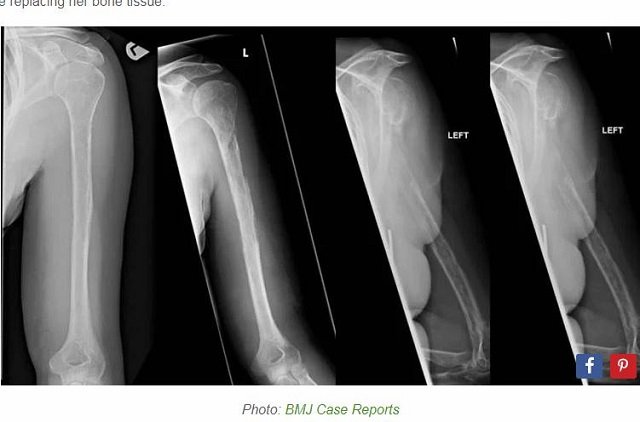

だが18カ月後、突如として病名が判明。医療チームが彼女のレントゲン写真をつぶさに検証し、ある驚異を発見したのだ。なんと、患者の上腕骨と尺骨が、レントゲンを撮るたび徐々に細くなっていく――ゴーハム病だった。

「Oddity Central」の記事より 別名「Vanishing Bones Syndrome(大量骨溶解症)」は、その名の通り、体内にある骨組織が溶けてゆき、線維性組織と拡張した壁の薄い血管に置換される奇病だ。きわめて稀な疾患であり、日本では平成27年7月1日から指定難病に登録されている。発症の原因はまったくわかっていない。ただ、遺伝性は認められないという。